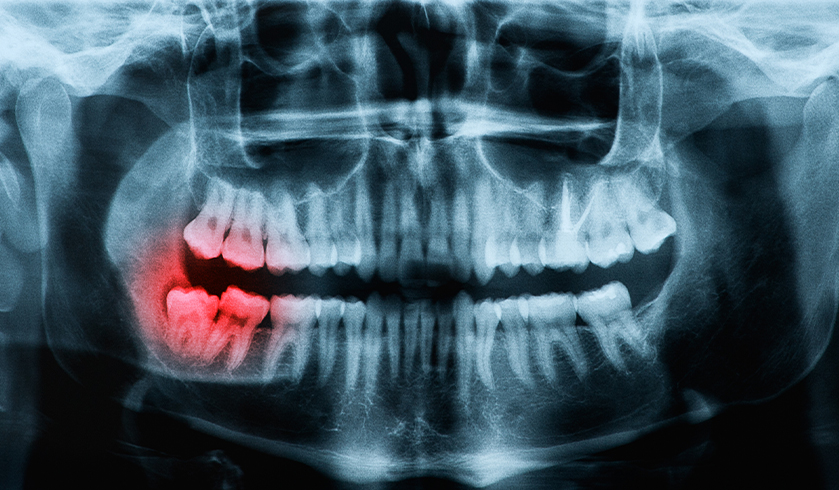

A root canal dental procedure may be necessary if a patient’s tooth/teeth become decayed or if an injury has occurred. In such cases, the tooth pulp usually becomes damaged, which can often result in a lack of blood to the area and, in turn, infection and tooth pain. Root canal treatment is essential to prevent infection from spreading, consequently saving the need for tooth extraction.

The infection requiring root canal treatment is typically very painful, causing a throbbing sensation in the are of the tooth and sometimes in the entire jaw. If left untreated, the pain may spread to the ears and can cause a constant headache. In some occasions, the infection may spread further and initiate flu-like symptoms, including fever and fatigue.